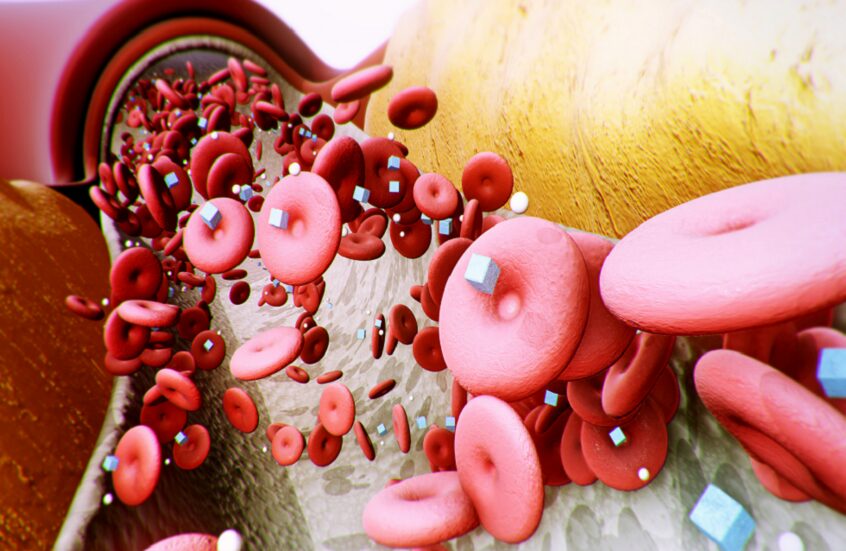

وبحسب موقع “interesting engineering”، “حصل هذا العلاج على تمويل قدره 344 ألف دولار من المؤسسة الوطنية للبحث والابتكار الطبي في أستراليا، ويحتوي الكريم على عقار فريد يسهم في تثبيط تكوين سرطان الجلد”.